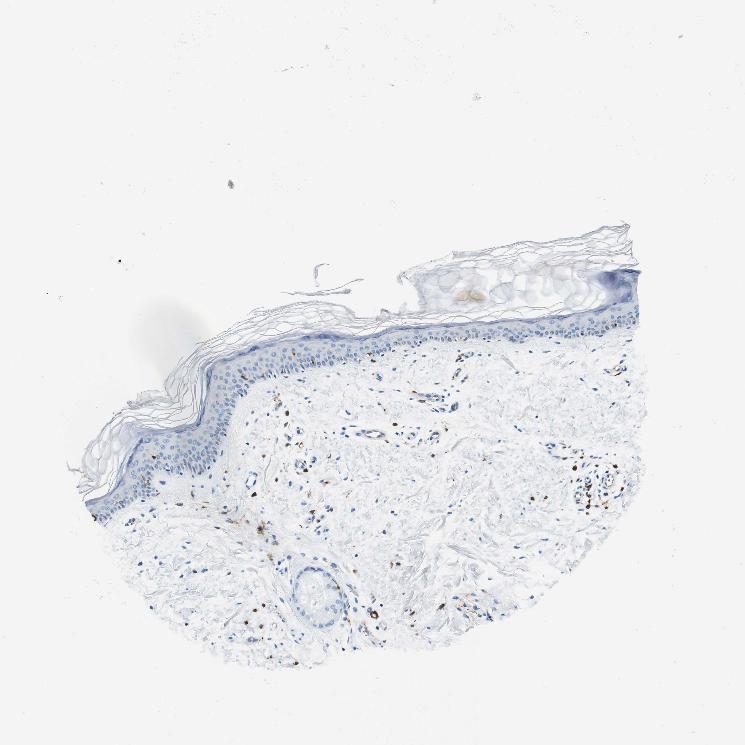

SKIN 1 - Antibody stainingi

Antibody staining in the annotated cell types in the current human tissue is reported as not detected, low, medium, or high, based on conventional immunohistochemistry profiling in selected tissues. This score is based on the combination of the staining intensity and fraction of stained cells.

Each image is clickable and will lead to virtual microscopy that enables deeper exploration of all samples and also displays staining intensity scores, fraction scores and subcellular localization as well as patient and tissue information for each sample.

Antibody HPA043151Antibody CAB015400Antibody CAB034021

Langerhans HighNot detectedNot detected

Fibroblasts Not detectedNot detectedNot detected

Keratinocytes Not detectedNot detectedNot detected

Melanocytes Not detectedNot detectedNot detected